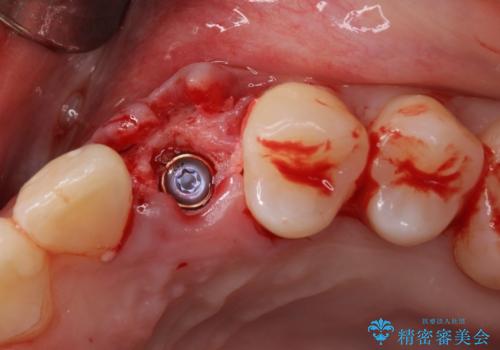

インプラントは、治療期間を短くすることが可能な、ストローマン社のSLActiveを使用することとしました。

インプラント治療は当初の狙い通り、矯正治療期間中に行い、スムーズに処置を進めることができました。